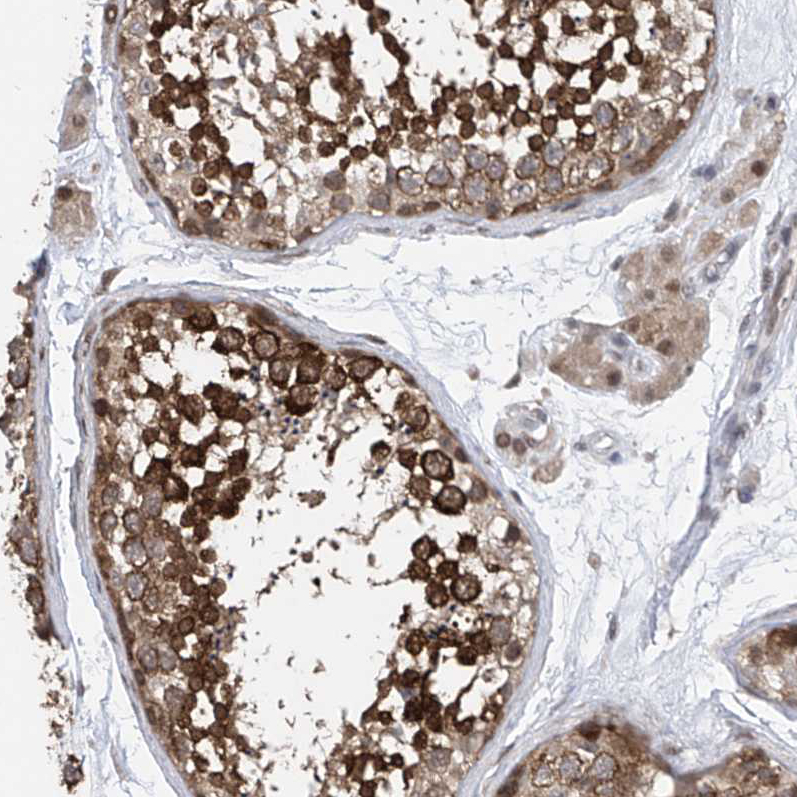

Immunohistochemical staining of human testis shows strong cytoplasmic positivity in cells in seminiferous ducts.